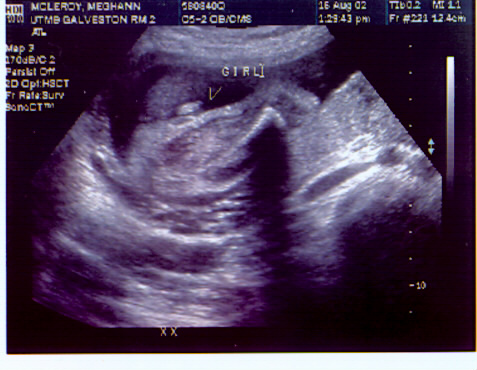

These are pictures from the ultrasound done on 8-16-02. I was at 25 1/2 weeks. I will try to explain them as best I can.

This is the shot that shows she is a she. She is in the position you put babies when you change their diaper. The arrow helps you see where to look. It is kinda a funky angle though.